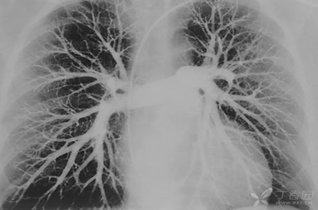

学会看胸片是临床医生必备的技能之一,首先,看胸壁的X线表现,观察胸壁软组织有大的肿块,有皮下积液、积气,同时观察肋骨的连续性是否有中断,这是肋骨骨折的X线征象...73227人收听

在临床上胸部X光片检查是常用的一种检查方法,它是利用X线产生图像,从而观察胸部的病变。胸片的观察需要按一定的顺序,一般可以按照从上往下的顺序,观察双肺上叶...1人收听